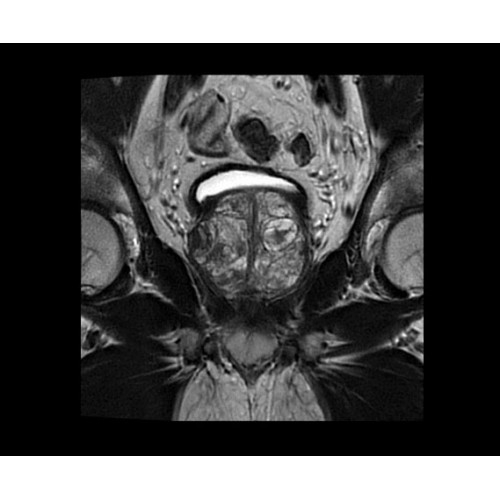

SIGNA PET/MR 3.0T — это гибридная система, в которой совмещаются две принципиально разные технологии — магнитно-резонансную томографию (МРТ) и позитронно-эмиссионную томографию (ПЭТ). Система отличающийся высокой чувствительностью и эффективностью и предназначена для диагностики в области онкологии, неврологии, кардио-васкулярных исследований, исследований воспалительных процессов.

Компания GE Healthcare представляет революционную, полностью интегрированную систему SIGNA PET/MR1, в которой сочетаются времяпролетная технология (TOF) и возможности напряженности магнитного поля 3.0 Тл. Мы поможем вам поднять исследования на более высокий уровень. SIGNA PET/MR позволяет достичь впечатляющей точности и скорости исследований, а благодаря новейшей технологии реконструкции Q.Clear2 качество изображений улучшается в два раза. Кроме того, в систему включен полный набор клинических приложений и гибких катушек для проведения любых видов исследования, открывая для вас возможности визуализации, о которых вы даже не догадывались.

Система SIGNA PET/MR предлагает впечатляющие клинические возможности и открывает доступ к наиболее полным пакетам программных приложений.